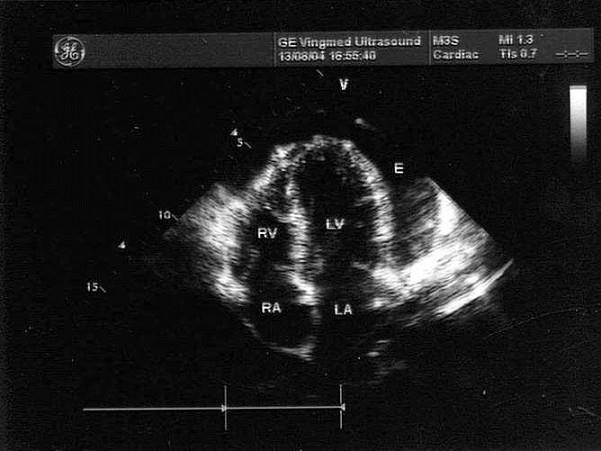

该病例最有可能诊断?(?)A.心包炎并心包积液B.心衰C.心包缩窄D.心包填塞E.胸腔积液

选项 A.心包炎并心包积液 B.心衰 C.心包缩窄 D.心包填塞 E.胸腔积液

答案 A